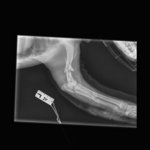

Wir treffen in Trikala, einer mittelgroßen Gemeinde auf dem griechischen Festland, ein. Vassiliki, eine 26-jährige Tierschützerin, die das Projekt an diesem Ort leitet und mich in den nächsten Tagen noch schwer beeindrucken wird, bringt uns direkt zu einer Tierarztpraxis, um Marla röntgen zu lassen. Außer den Vordergliedmaßen ist nichts gebrochen und auch die inneren Organe scheinen nicht verletzt zu sein. Dann bleibt „nur“ noch die Großbaustelle: ihre beiden vorderen Beinchen. Sie sind insgesamt an vier Stellen gebrochen. Welch himmelschreiende Ungerechtigkeit! Rechtzeitig vor einem elendigen Sterben am Straßenrand gerettet worden zu sein und dann vor nahezu unlösbaren Problemen zu stehen? Ich selber habe hier weder die Möglichkeiten, noch das Equipment, um Brüche zu operieren. Aber kapitulieren werden wir nicht. Keiner von uns. Auch Marla nicht, das haben wir uns beide ganz leise aber ganz fest versprochen.

Wenige Tage später ist Marla operiert. Mehrere Operationen waren erforderlich, um die komplizierten Brüche zu versorgen. Chirurgische Höchstleistungen machten es möglich, ihre Beine zu erhalten.